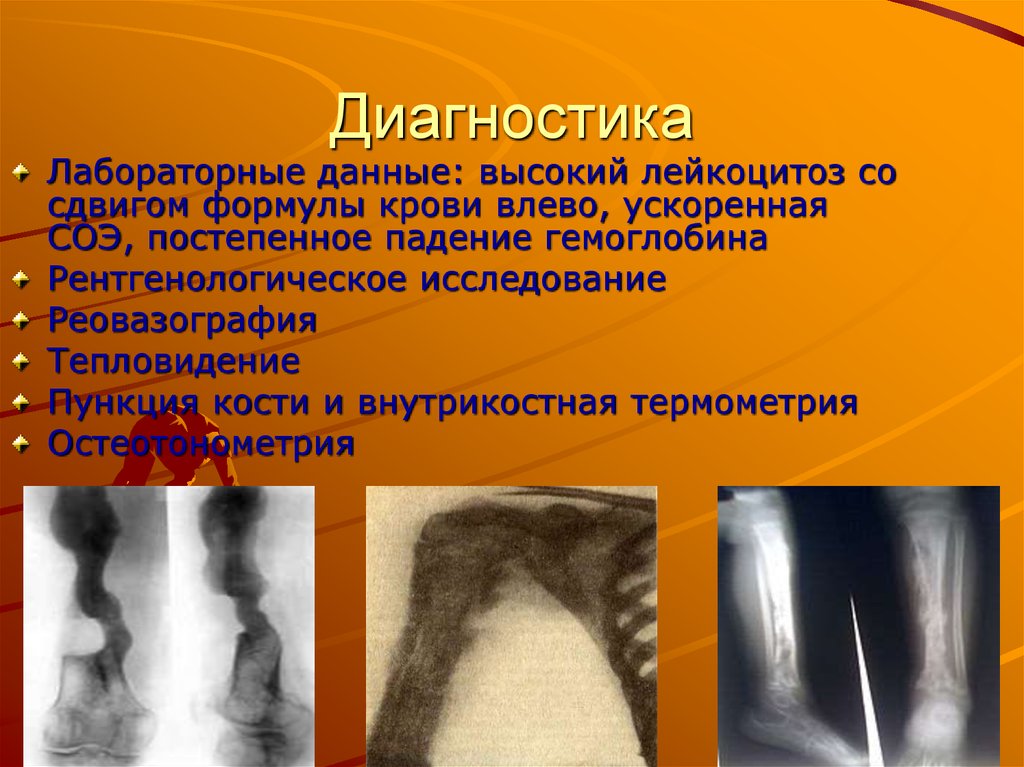

Рентгеновские снимки посттравматического остеомиелита челюсти: Медицинские случаи

Раздел: Образы вокруг